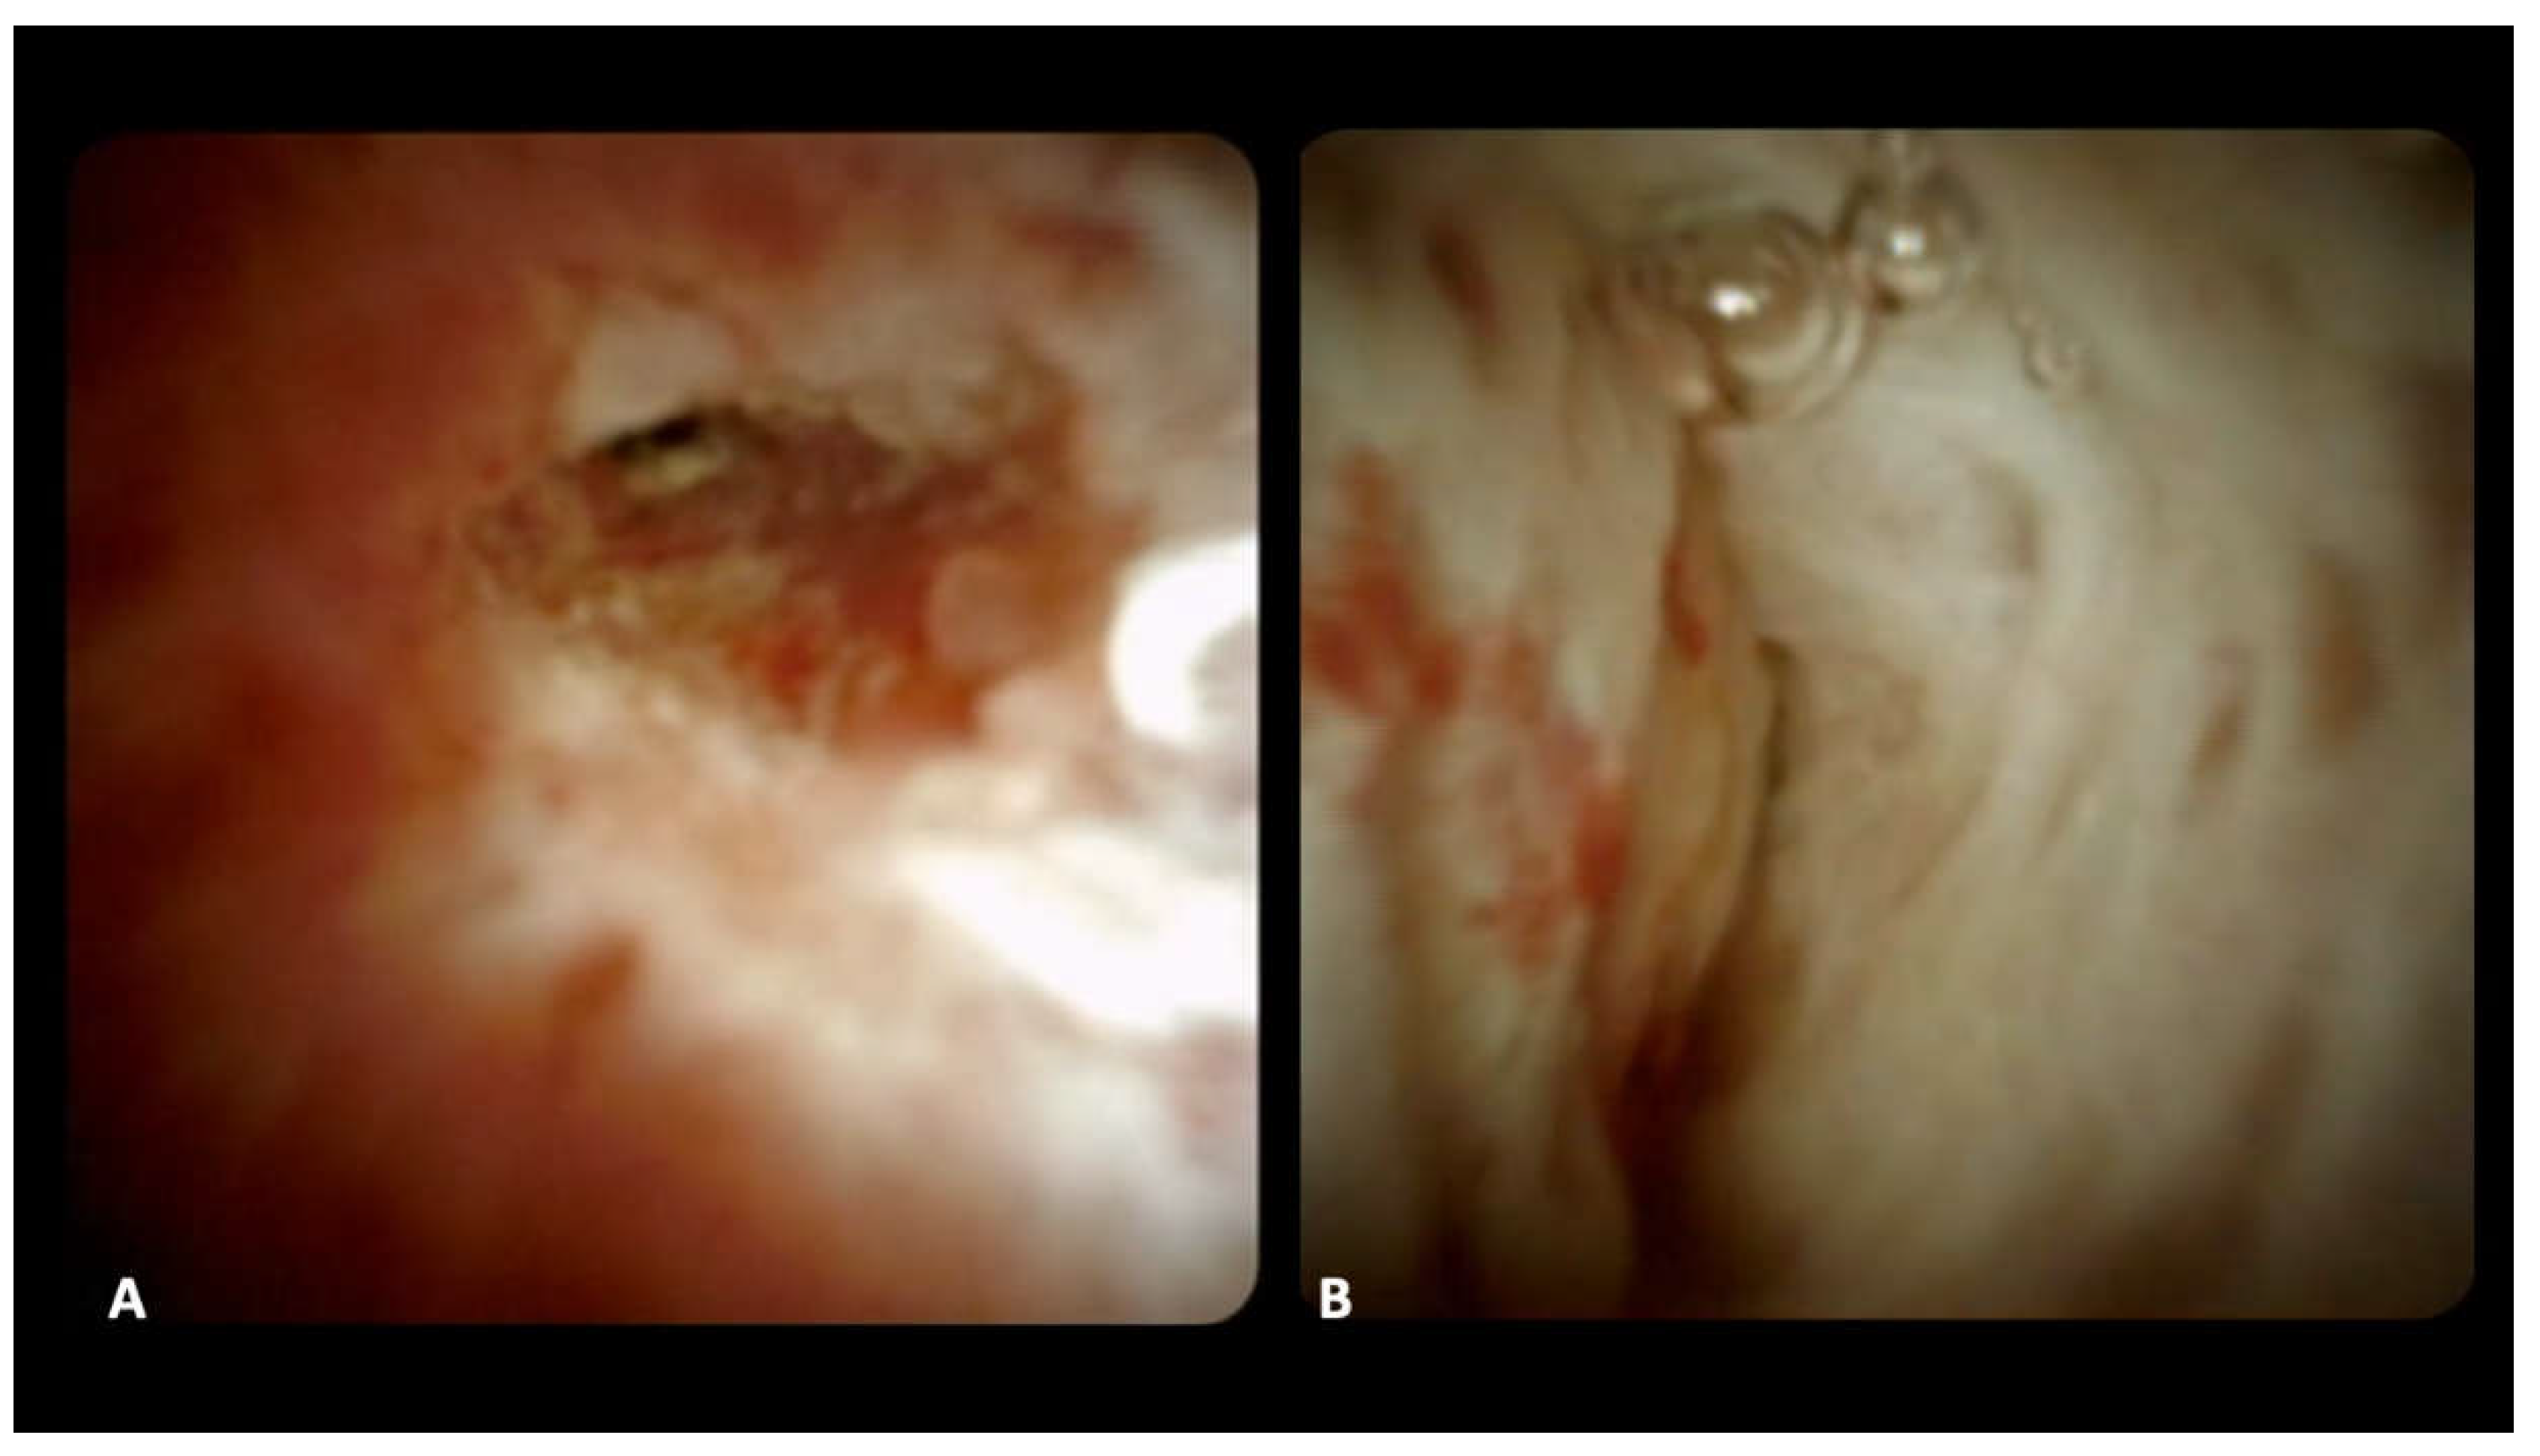

For DSOC-based diagnosis, the presence of the following criteria was evaluated: (1) stricture, (3) mucosal changes, (4) papillary projections, (5) ulceration, (6) mass or nodularity, and (7) vascularization [11]; the final impression diagnosis of benign or malignant stricture was made during the procedure (Figure 1).

Figure 1. Cholangioscopic images of a malignant stricture with irregular mucosa and enlarged irregular vessels (a), and a benign stricture, with smooth whitish biliary epithelium with fibrotic appearance (b).